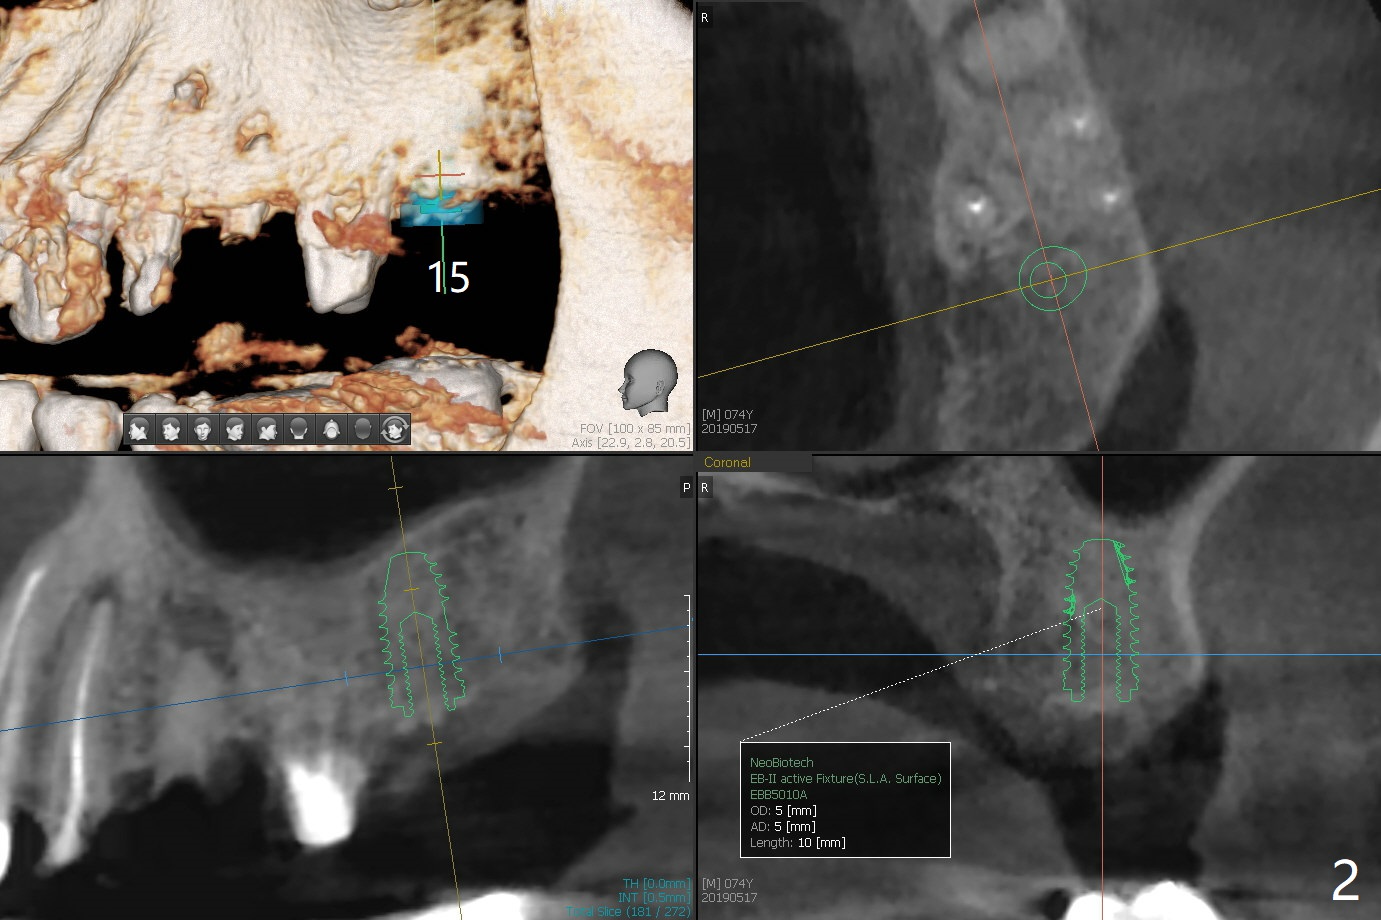

Reach Depth First with Guide

A 74-year-old man with multiple crowns and FPD needs implants at #13 and 15 (Fig.1). To avoid drills or implant (particularly immediate one) touching the neighboring root, 2.2 mm drill will reach the depth (sequentially) first and take segmental panoramic X-ray. Then return to the original sequence: diameter first and depth second to avoid bone necrosis.